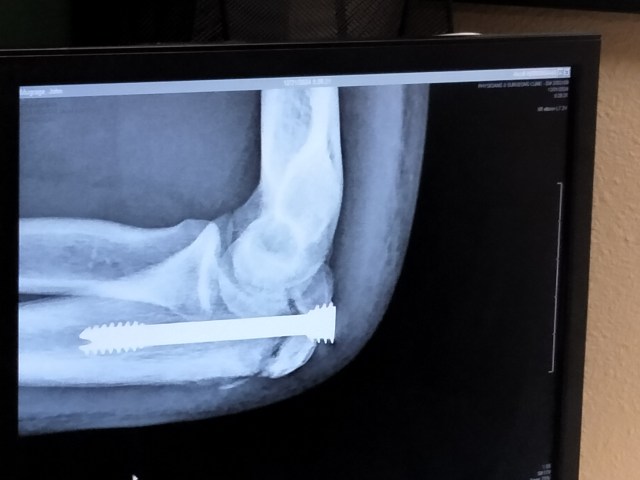

It might! The injury put a stop to violence for the latter part of football season … but we trust he will be able to resume violence next year. 🙂